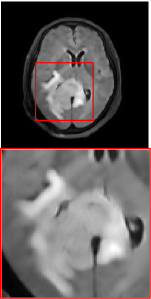

Figure 5 provides the qualitative comparison of the various methods on the four datasets at a scale of 4. The top, second, third, and bottom rows are the SR results under the FastMRI, clinical brain, clinical tumor and clinical pelvic datasets, respectively. The red boxes indicate the zoom-in region of complicated anatomical structures along with their corresponding error maps. Note that the brighter textures in the error maps, the lower the quality of the reconstructed images. As can be seen, compared to methods based on Transformers and CNNs, diffusion-based methods like DisC-Diff and DiffMSR (Ours) are capable of reconstructing high-realistic images with promising reconstruction metric scores (PSNR and SSIM). Nevertheless, while DisC-Diff can reconstruct high-precision MR images, it does not preserve the structure present in the original HR images, introducing some additional information that can affect medical diagnosis. In contrast, our method combines DM and PLWformer, which can preserve the original image’s structure while restoring high-frequency information.